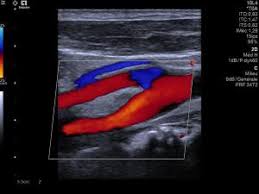

L’Échographie utilise des ultrasons (ondes sonores à haute fréquence) pour visualiser en temps réel les organes, les vaisseaux et les tissus mous du corps. C’est un examen non invasif, indolore et qui n’utilise pas de rayons ionisants. L’Écho-Doppler est un complément indispensable qui mesure la direction et la vitesse de la circulation sanguine (flux).

Exploration des structures vasculaires (flux sanguin) du cou, des membres et de l'abdomen.